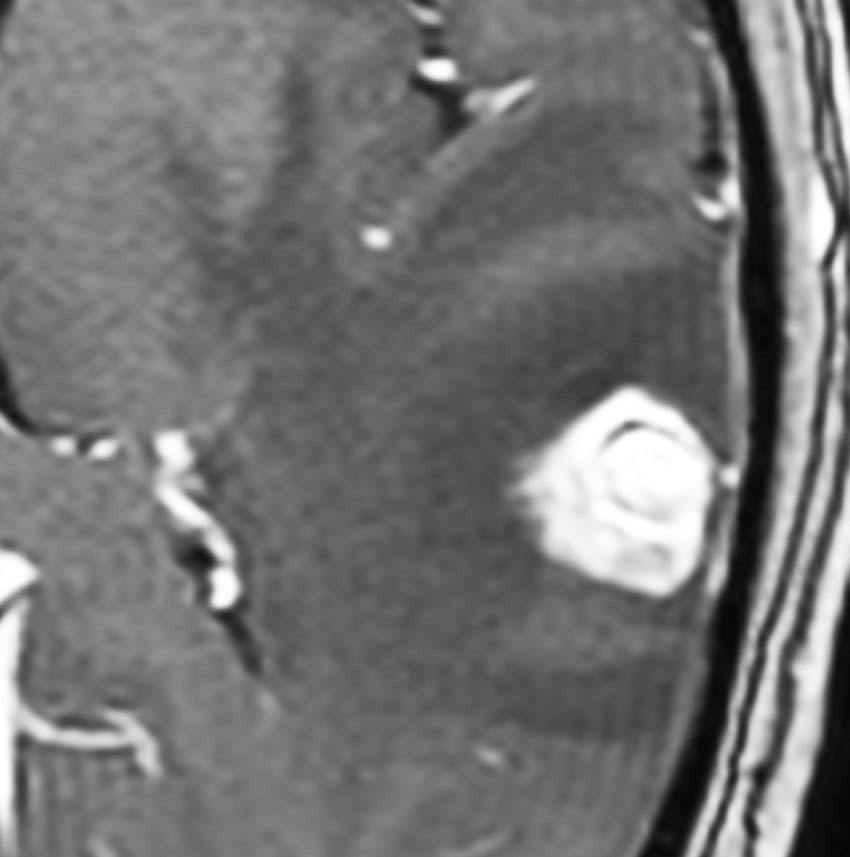

典型的な転移性脳腫瘍(単発)のMRI

腺癌の左前頭葉転移です。左のガドリニウム造影剤を使った画像では腫瘍が白く写っています。腫瘍の内部が一部壊死しているので黒っぽく見えます。右はフレア画像です。腫瘍の周囲の脳が腫れて脳浮腫(白く滲むようなところ)を生じています。

開頭手術で摘出した半年後の画像です。腫瘍は再発していなくて,脳の腫れも引いています。転移が発見された時には,見当識障害などの左前頭葉症状が強かったし,摘出がとても簡単な場所だったので手術しました。線状皮膚切開・小開頭ですから1時間くらいの簡単な手術です。でも,26mmくらいでしたから,定位放射線治療も可能なものでした。この患者さんは幸いなことに半年で再発していませんが,開頭手術による摘出だけだと同じ場所からまた再発することもあり,それから放射線治療を加えなくてはならないこともあります。個々の判断は難しいのですが,基本的には開頭手術より定位放射線治療のほうがいいと考えて下さい。